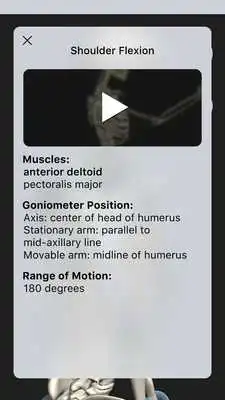

OT Kinesiology Pro Consult is a resource to learn how to correctly and accurately measure joint range of motion.See the movement being measured in clinic, highlighting goniometer placement and the prime muscles involved in an animated 3D skeleton.

Tap joints on the skeleton to view flexion contentMuscles associated with each flexion

Anatomical reference and clinical video examples for each flexion